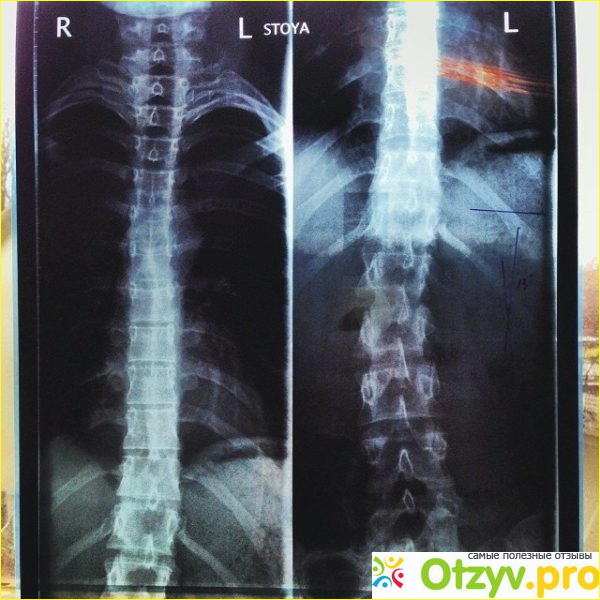

Так вот проблема вся заключалась в том, что под действием удара фильтра у меня произошло смещение ряда позвонков, при этом положение позвоночника изменилось, происходило защемление нервных окончаний, которые как раз и вызывали эти дикие боли. Сама мануальная терапия прошла очень удачно, работали со мной два врача, один меня отвлекал и помогла принять правильное положение, а второй мне вставлял на место позвонки. Я даже не чего не чувствовал, ну только что был резкий щелчок, когда позвонки вставали в свое нужное место. В конечном итоге мне вправили 7 позвонков, а это довольно прилично, после чего я мог спокойно встать на ноги и продолжить движение, но врачи меня сразу не отпустили.